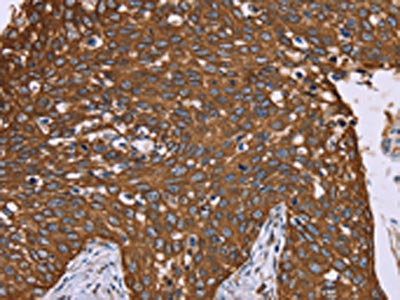

• The image on the left is immunohistochemistry of paraffin-embedded Human cervical cancer tissue using CSB-PA906437(PPIB Antibody) at dilution 1/40, on the right is treated with fusion protein. (Original magnification: ×200)

• The image on the left is immunohistochemistry of paraffin-embedded Human liver cancer tissue using CSB-PA906437(PPIB Antibody) at dilution 1/40, on the right is treated with fusion protein. (Original magnification: ×200)